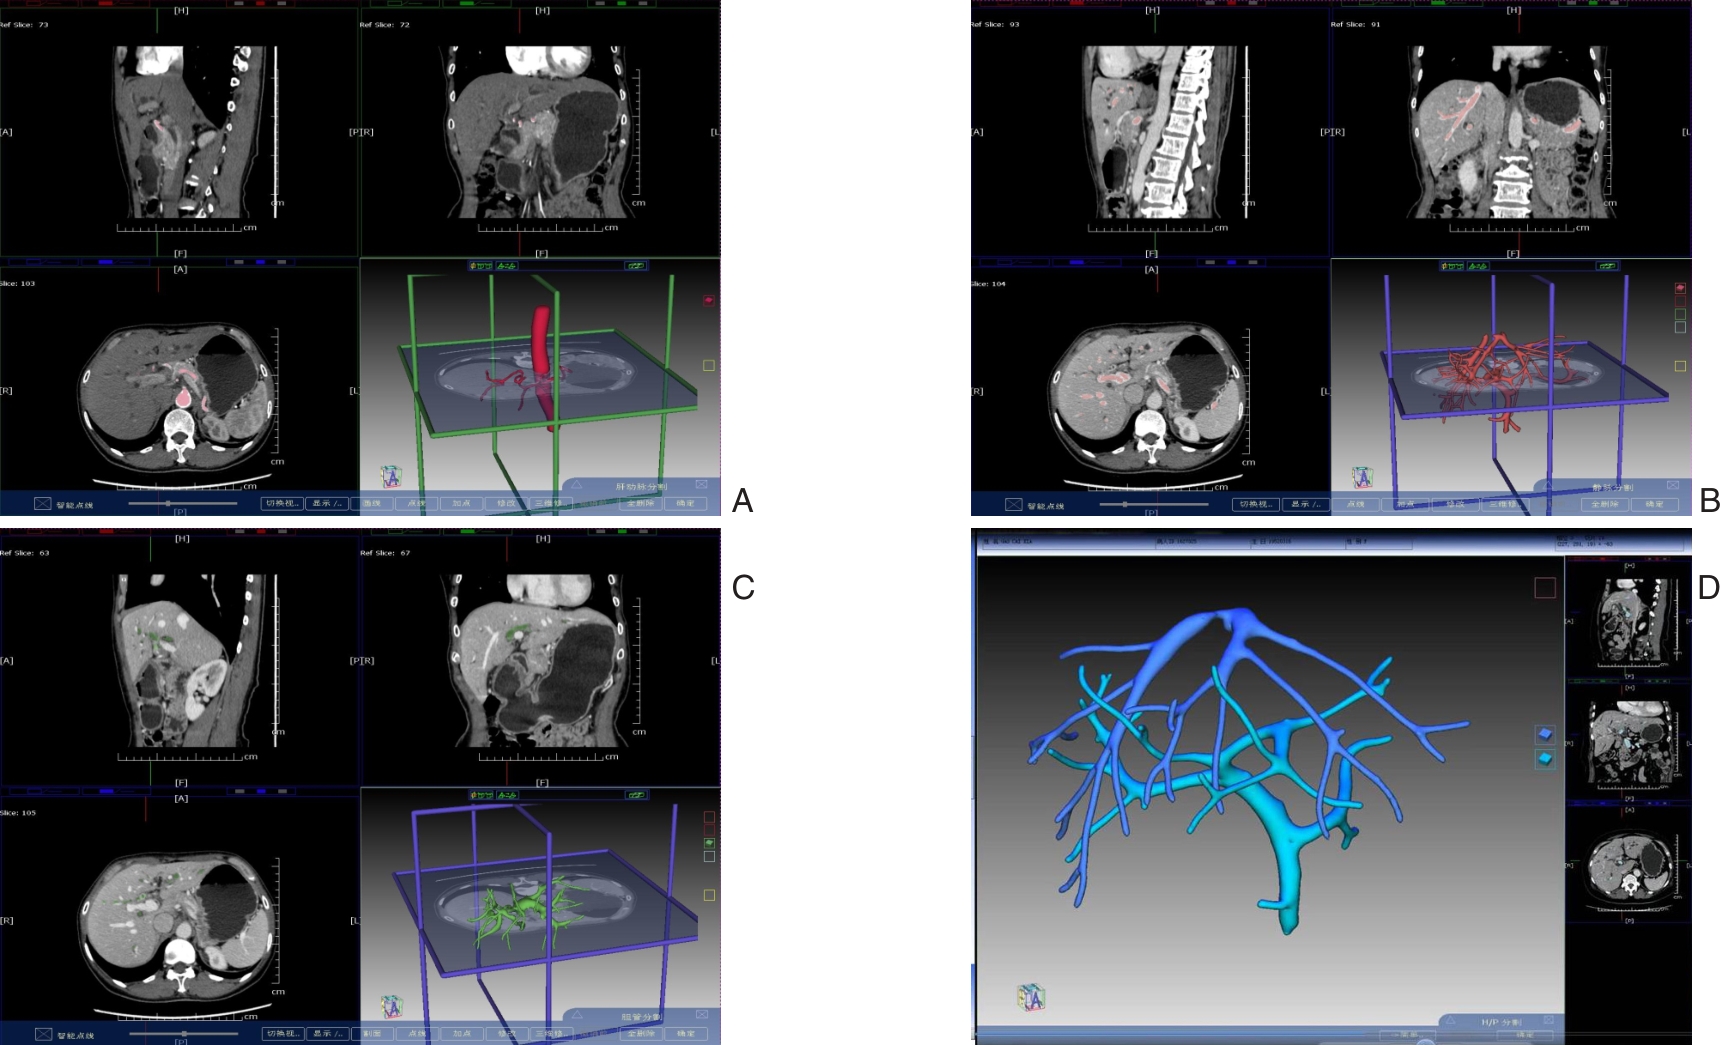

SHEN Zhengchao, CHEN Zhiyuan, XI Shihang, PAN Xuan, QIAN Daohai, MUHAMMAD Danish Irshad, WANG Xiaoming

2026,35(1):88-96, DOI: 10.7659/j.issn.1005-6947.250468

Abstract:

Background and Aims Laparoscopic resection of centrally located hepatic tumors remains technically demanding due to the complex anatomical relationships with major vascular structures. Conventional intraoperative ultrasound or indocyanine green fluorescence imaging (ICG-FI) alone has limitations, particularly in visualizing deep anatomical structures. This study aimed to evaluate the clinical value of augmented reality (AR) navigation combined with ICG-FI in laparoscopic resection of central hepatic tumors.Methods A retrospective analysis was conducted on 38 consecutive patients who underwent laparoscopic resection of central hepatic tumors guided by AR navigation combined with ICG-FI between May 2022 and March 2025. Intraoperative navigation performance, surgical parameters, and perioperative outcomes were assessed.Results All 38 procedures were completed laparoscopically without conversion. The intraoperative tumor fluorescence detection rate was 100%. The mean operative time was (324.9 ± 132.4) min, and the median intraoperative blood loss was 400 (50-1 200) mL. The mean registration error was (6.3±0.6) mm. The median number of predicted and verified vessels was 6 (4-8) and 7 (5-10), respectively. R0 resection was achieved in all patients, with a mean surgical margin of (1.5±0.5) cm. The postoperative complication rate was 13.2%, with no severe complications such as intra-abdominal hemorrhage, gas embolism, or liver failure. The median postoperative hospital stay was 9 (4-20) days. During a median follow-up of 20 months, no tumor recurrence was observed.Conclusion The combined use of AR navigation and ICG-FI enables intraoperative prediction and verification of critical vascular structures and facilitates precise control of the transection plane in laparoscopic resection of central hepatic tumors. This technique improves surgical precision and safety and shows promising clinical potential.